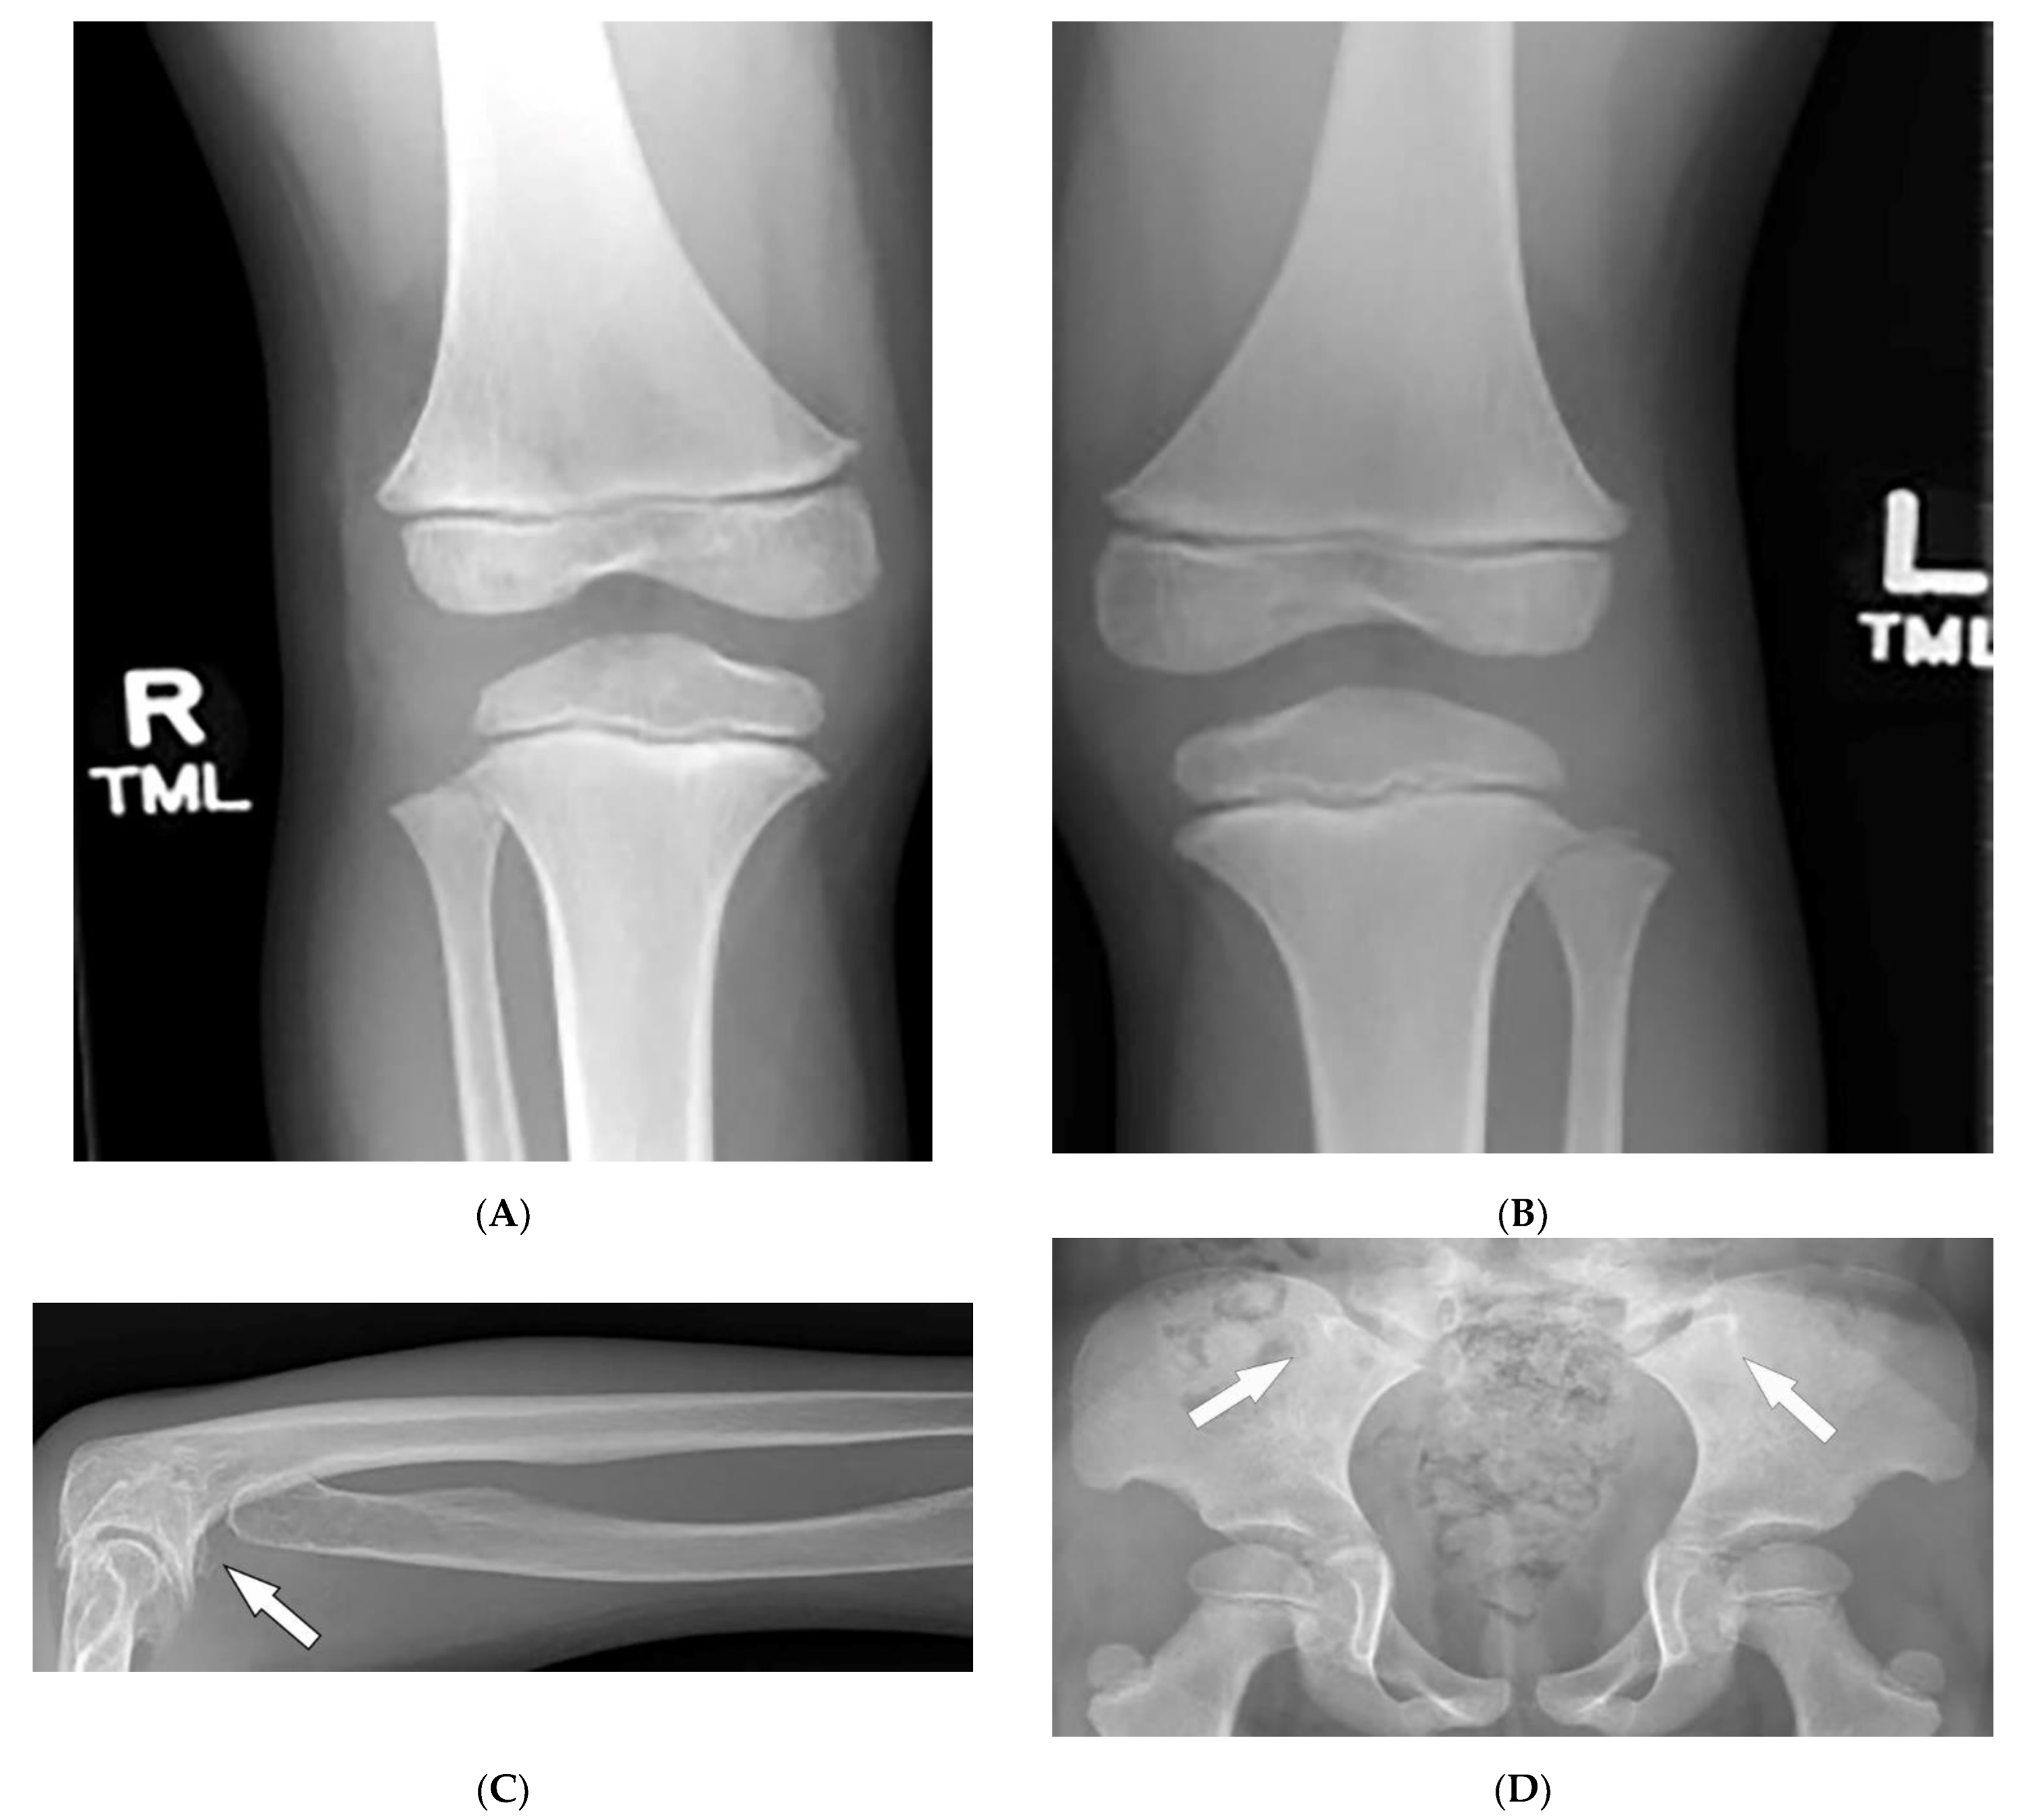

| Fong (Nail–patella) syndrome | Hypoplastic nails, triangular lunulae Hypoplastic patellae Focal segmental glomerulosclerosisLester iris | Bilateral absence of patellae Posterior iliac horns (Fong’s prongs) Subluxation of radial heads |

| Buschke–Ollendorff syndrome | Dermatofibrosis lenticularis disseminata Osteopoikilosis Melorheostosis | Bony islands and multiple sclerotic lesions cause mottled appearance Cortical thickening with undulating bone |